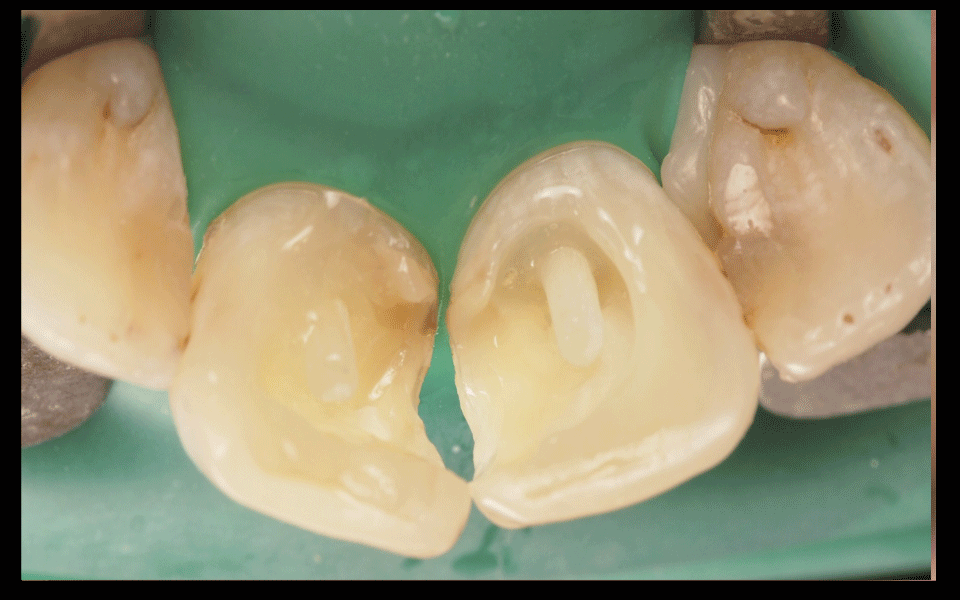

Основное преимущество работы под микроскопом. 20-кратное увеличение позволяет бережно обрабатывать зуб и удалять только поврежденные ткани. Зуб препарируется (обтачивается) высокоточно.

Краевое прилегание пломбы – это качество соединения пломбы с тканями зуба. Именно краевое прилегание пломбы обеспечивает герметичность зуба. Пломба, которая идеально плотно прилегает к зубу простоит очень долго. Под микроскопом значительное увеличение позволяет проконтролировать герметичность пломбы, идеально пришлифовать пломбу к зубу и гарантировать ее долговечность.

Установленная под микроскопом пломба простоит в 2 раза дольше, ведь врач под увеличением проверит качество прилегания пломбы к зубу, а значит обеспечит ее герметичность. Любое воспаление под пломбой возникает при нарушении ее герметичности. С применением микроскопа пломба содержит большее количество слоев пломбировочного материала. Под значительным увеличением врач аккуратно слой за слоем восстановит разрушенный зуб повторяя структуру ткани идентично живому зубу, внутри будет более прочный материал для распределения нагрузки, а снаружи более прозрачный для естественной белизны и преломления света. Диагностика кариеса под микроскопом обладает высокой точностью. При помощи микроскопа врач не пропустит начальный кариес, увидит кариес в стадии пятна, обнаружит трещины и сколы. При ранней диагностики кариеса без сверления и без бормашины можно остановить кариес специальными изоляционными пломбировочными материалами. Зубу будет возвращена герметичность, а вы никогда не узнаете, что такое зубная боль.

Прилегание пломбы

пломба будет стоять долго если она будет идеально прилегать к зубу.